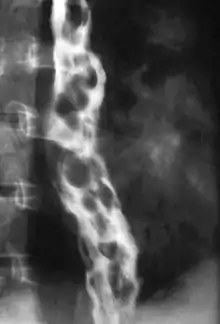

X-ray of a person with dilated, snake like varicose veins in their esophagus secondary to pulmonary hypertension.